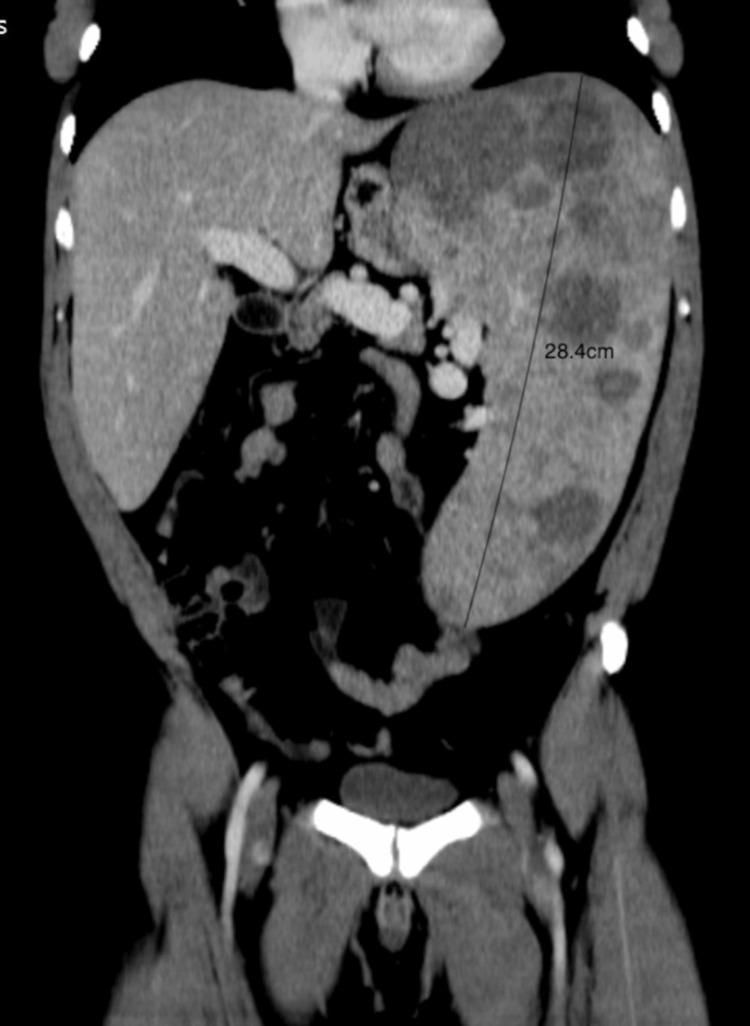

Gaucher disease (GD) is a recessive autosomal lysosomal storage disorder caused by a deficiency in glucocerebrosidase, leading to the accumulation of undigested glycolipids in the lysosomes of monocytes and macrophages. Patients with GD exhibit a spectrum of phenotypic heterogeneity and are broadly classified into three subtypes. Type 1 is the most common and is not associated with neurological damage, while types 2 and 3 are more severe, presenting with acute neuropathic and subacute neuropathic symptoms, respectively. A thorough accurate initial multisystemic assessment is crucial for evaluating the damage to all potentially affected organs and determining the disease burden. This case report highlights the intricacies of GD type 1 by providing a thorough exploration of the clinical presentation and showcasing valuable insights into the unique manifestations of the disease. The key feature was his individual and family medical history, which allowed the identification and treatment of another case within the community.

戈谢病(GD)是一种常染色体隐性溶酶体贮积症,由葡糖脑苷脂酶缺乏引起,导致未消化的糖脂在单核细胞和巨噬细胞的溶酶体中蓄积。戈谢病患者表现出一系列表型异质性,大致分为三个亚型。1型最为常见,与神经损伤无关,而2型和3型更为严重,分别表现为急性神经病变和亚急性神经病变症状。全面准确的初始多系统评估对于评估所有潜在受累器官的损伤以及确定疾病负担至关重要。本病例报告通过深入探讨临床表现并展示对该疾病独特表现的宝贵见解,突出了1型戈谢病的复杂性。关键特征是他的个人和家族病史,这使得能够在社区内识别并治疗另一例病例。